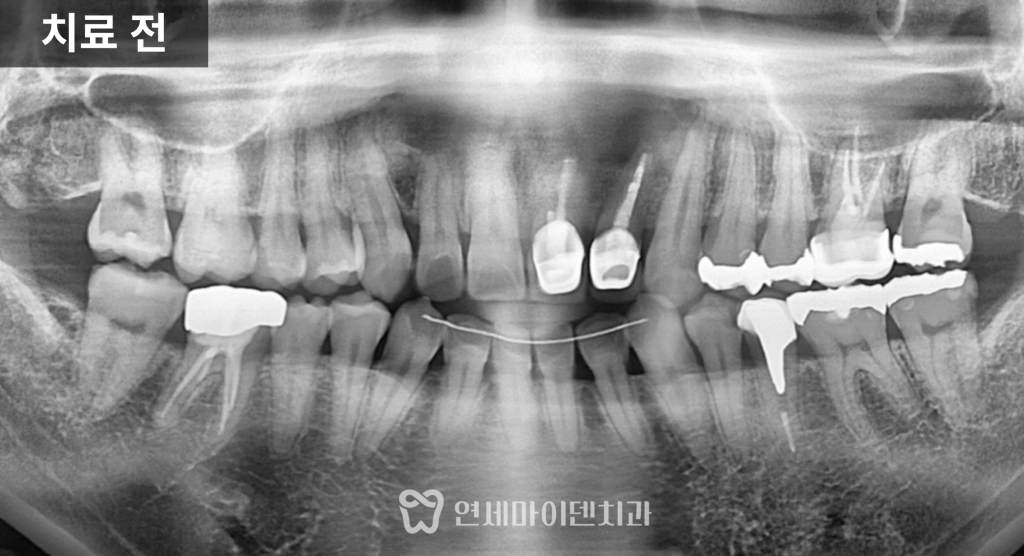

치료 전 엑스레이를 보면

앞니는 이미 신경치료 후 크라운까지

마무리된 상태였습니다.

다만 한쪽 치아의 뿌리 끝에만

둥글게 뼈가 녹아 있는

큰 염증

이 관찰되었습니다.

이처럼 동그랗게 경계가 명확한 염증은

치근단 낭종 형태의 염증일 가능성이 높고,

대부분 신경관 내부의 감염이

완전히 제거되지 않았을 때

발생

하는 경우가 많습니다.

즉, 겉으로는 치료가 끝난 상태처럼 보여도

치아 내부에서는 감염이 지속되고 있었던 상황입니다.

재신경치료 후 약 6개월이 지나자

뿌리 끝에 있던 염증은 점차 줄어들고

뼈가 다시 차오르는 양상이 확인되었습니다.

결과적으로 치근단 절제술이나 발치 없이

재신경치료와 크라운만으로

치아를 보존

할 수 있었습니다.